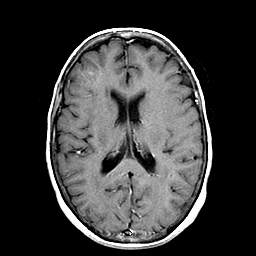

Metastatic Adenocarcinoma of the Colon: T1-weighted MR -- Slice #14

[Home][Help][Clinical] Slice 14